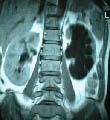

其中,B超是筛查肾癌最合适的方法之一,可发现直径08cm的肾肿瘤。如果B超发现异常者,应进行CT检查,该方法可发现05cm以上的肿瘤,仍不能确诊者还要进行核磁共振检查。